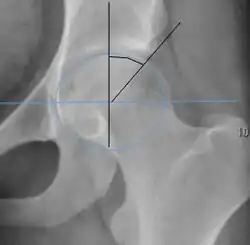

| Alpha angle | ![]() |

Degree of bulging of the femoral head-neck junction: In normal conditions there is a symmetric concave contour at the junction of the femoral head and neck. Loss of this concavity or bone bulging may lead to cam type impingement. The degree of this deformity can be measured by the alpha angle. Although it can be measured in the cross-lateral view, the 45° Dunn view is considered more sensitive and the frog leg view more specific in determining pathologic values. |

|